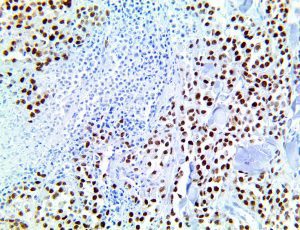

It is the ICU physician who is most likely to witness one of the deadliest manifestations of the abnormal immunological response, the cytokine storm syndrome (CSS). This response is also referred to by some as the cytokine release syndrome (CRS). CSS is characterized by continuous activation and expansion of macrophage and lymphocyte populations, which secrete large amounts of cytokines, causing the cytokine storm. This massive cytokine release is akin to hemophagocytic lymphohistiocytosis (HLH) disease, a syndrome characterized by initial unchecked and persistent activation of cytotoxic T lymphocytes and NK cells.

Clinical and laboratory manifestations of HLH include fever, enlarged liver and/or spleen, neurologic dysfunction, coagulopathy, liver dysfunction, cytopenias (i.e., low levels of erythrocytes, leukocytes, and/or platelets), hypertriglyceridemia, hyperferritinemia, hemophagocytosis, and eventually diminished NK cell activity as the immune system becomes progressively paralyzed. HLH can be familial (primary HLH) or secondary to another disease process (sHLH), such as rheumatic disease, in which it is referred to as macrophage activation syndrome (MAS, characterized by elevated ferritin).